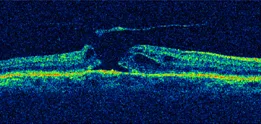

Degeneration of the neurosensory retina at the macular region can lead to gross deterioration of vision, a condition that is referred to as “Macular Hole”.

Membrane Peeling for treating conditions like Macular Hole

THE MAGIC OF MACULAR HOLE SURGERY